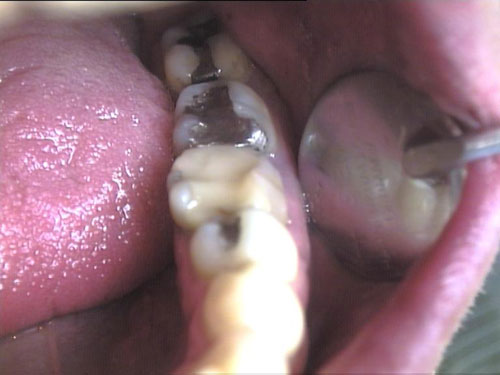

Brückenersatz